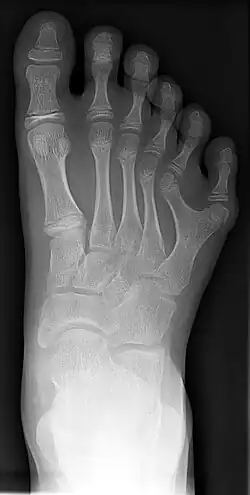

Röntgenfoto van voet met 6 tenen